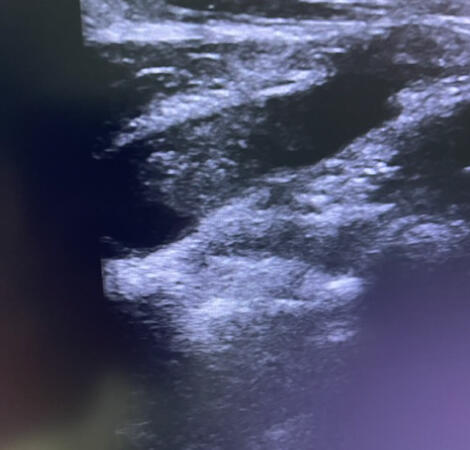

Η διάγνωση και η θεραπεία του ΣΘΕ μπορεί να περιλαμβάνει κλινική εξέταση, εικονολογικές εξετάσεις (όπως ακτινογραφίες, υπερηχογραφίες), και σε ορισμένες περιπτώσεις, ηλεκτροδιαγνωστικές εξετάσεις για την αξιολόγηση της νευρομυϊκής λειτουργίας.